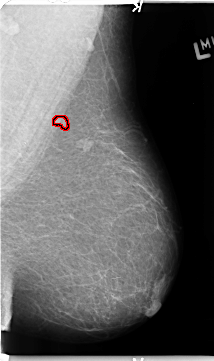

B_3153_1.LEFT_MLO

LEFT_MLO LINES 4688 PIXELS_PER_LINE 2776 BITS_PER_PIXEL 12 RESOLUTION 50 OVERLAY

FILE: B_3153_1.LEFT_MLO.OVERLAY

TOTAL_ABNORMALITIES 1

ABNORMALITY 1

LESION_TYPE MASS SHAPE IRREGULAR MARGINS ILL_DEFINED-SPICULATED

ASSESSMENT 4

SUBTLETY 3

PATHOLOGY BENIGN

TOTAL_OUTLINES 1

BOUNDARY